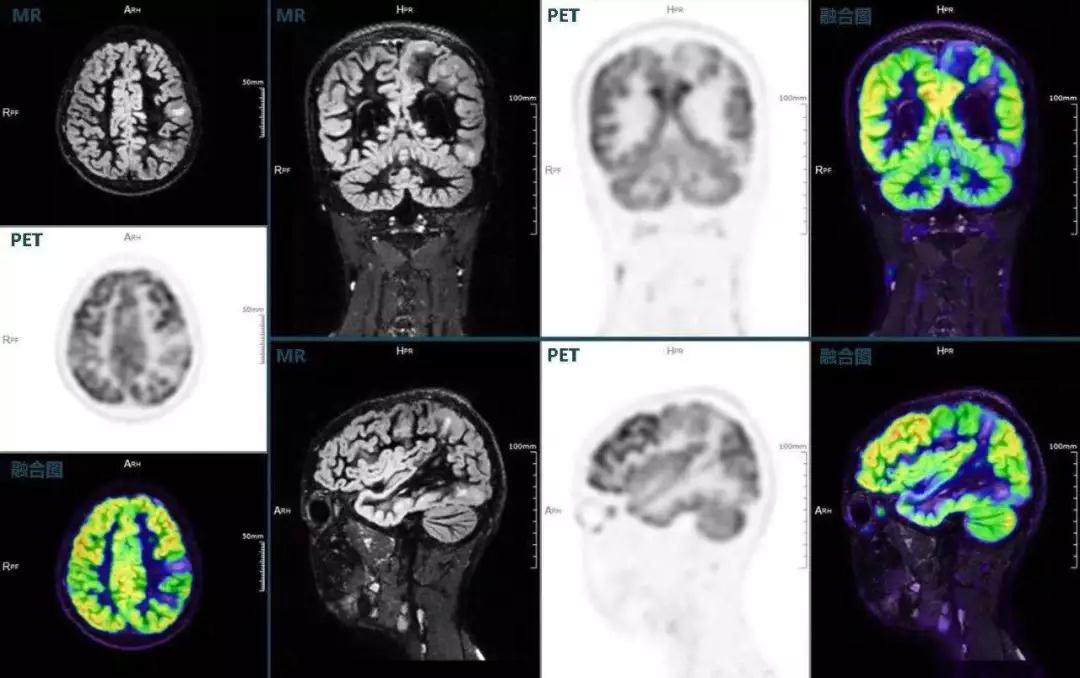

不僅如此,聯(lián)影“時(shí)空一體”超清TOF PET/MR還搭載了大量可用于神經(jīng)疾病領(lǐng)域的高級(jí)應(yīng)用,如DIR(Double Inversion Recovery雙反轉(zhuǎn)恢復(fù))序列能夠清晰顯示大腦皮層的結(jié)構(gòu)成像,對(duì)于皮層腫脹,膠質(zhì)增生等癲癇的影像征象都能清楚呈現(xiàn);DTI(Diffusion Tensor Imaging彌散張量成像)高級(jí)應(yīng)用能夠顯示細(xì)小的神經(jīng)纖維束缺損,以更加定量的形式為醫(yī)生提供一個(gè)全新的診斷維度,輔助醫(yī)生精準(zhǔn)診斷。

(結(jié)節(jié)性硬化,MR DIR序列清晰顯示腦皮層病理改變,PET顯示了病灶區(qū)域FDG的低濃聚。PET/MR融合顯像同時(shí)提供了結(jié)構(gòu)異常改變和功能變化的信息。)